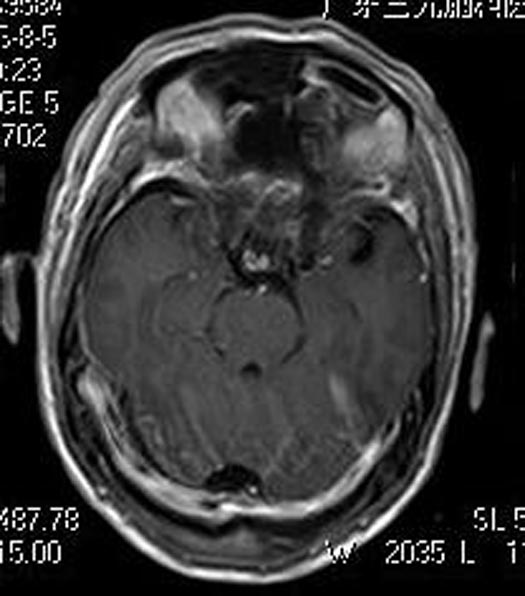

儿女们认为父亲视力下降肯定是有原因,在孩子们的劝说下,申先生来到广东三九脑科医院综合神经外科。头颅MR检查提示:前颅底占位病灶,考虑颅底脑膜瘤(大小约49.9mm×47.0mm×25.0mm),瘤灶后缘挤压视交叉。头颅CTA检查提示:前颅窝底占位性病变血管丰富,与双侧大脑前动脉A1、2段关系密切,考虑脑膜瘤。

鲁明主任告诉申先生:肿瘤继续压迫将会对视神经产生不可逆的损害。家属积极地要求手术治疗。由鲁明主任主刀,在全麻下行经右额前颅底巨大脑膜瘤切除术,术中见白色肿瘤,质韧,边界清,肿瘤与右视神经大脑前有粘连,视交叉及右视神经受肿瘤压迫,锐性分离肿瘤与神经、肿瘤与血管、以相同手术跨大脑镰分离左颅底肿瘤、肿瘤与左侧视神经,镜下全切肿瘤,解剖保留双侧视神经、神交叉,双侧大脑前动脉,手术顺利。术后申先生视力明显好转,病理结果提示:过渡型脑膜瘤 WHO I级。